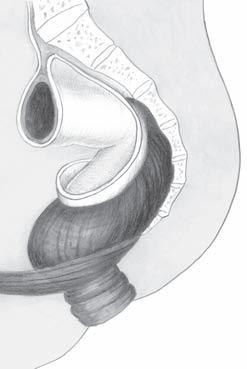

pánevního. V avaskulárním prostoru mezi viscerálním a parietálním listem presakrální fascie probíhají nervi hypogastrici, které lze vizuálně identifikovat při ostré preparaci (obr. 2.7). Jak bylo uvedeno výše, viscerální rektální fascie extraperitoneálně posterolaterálně ohraničuje mezorektum. Anatomicky je název „mezorektum“ nepřesný. V chirurgické literatuře se tento termín běžně používán pro tukovou tkáň obklopující jako polštář rektum, v které probíhají cévní a lymfatické svazky zásobující rektum, vasa rectalis superior a vasa rectalis media. Mezorektum začíná od promontoria jako pokračování mezosigmoidea a končí na Waldeyerově fascii, tedy na dně pánevním. Laterálně nacházíme v mezorektu pevnější vazivové struktury, obkružující vlákna autonomních nervů, která přicházejí k rektu z pelvického plexu. Tyto struktury jsou známy jako laterální ligamenta či paraprokcia a spojují stěnu malé pánve s mezorektem. Při totální excizi mezorekta je doporučována resekce laterálních ligament s následnou ligaturou tak, aby byla zachována integrita mezorekta a byly ligovány jen nervové pleteně inervující rektum. Podobně i ostrá disekce v avaskulárním prostoru mezi parietálním a viscerálním listem presakrální fascie zachová integritu mezorekta a uchrání autonomní nervové svazky. Vpředu je fascia visceralis recti (fascia propria) tenčí než vzadu a splývá s přední stěnou rekta. Rektum je ale od pohlavních orgánů odděleno denonvillierskou fascií, která je z hlediska embryologie reziduem dvouvrstevného slepého vaku peritonea (obr. 2.8). Denonvilliers popsal prostatoperitoneální fascii u mužů, ekvivalentní vrstvu lze však najít i u žen – fascia rectovaginalis. Vzhleprostata

stěna rekta mezorektum fascia visceralis fascia parietalis

os sacrum

Obr. 2.7 Zadní disekce mezorekta

dem k tomu, že vývojově jde o zbytek slepého peritoneálního výběžku, lze sledovat u dennonvillierské fascie jednu vrstvu adherující k semenným váčkům a prostatě a druhou vrstvu naléhající těsně na přední plochu rekta.

Obr. 2.8 Přední disekce u muže mezorekta